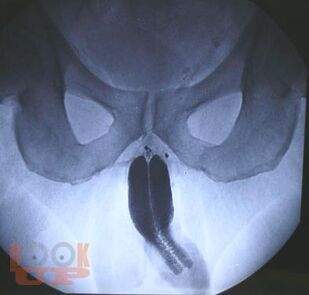

Динамическая кавернозография в диагностике патологии кавернозного бассейна полового члена

В учебном пособии представлены вопросы метода рентгеновского исследования заболеваний кавернозного бассейна полового члена, некоторые анатомо-физиологические аспекты эрекции, показания и противопоказания к проведению динамической кавернозографии, описана методика проведения динамической кавернозографии, а также представлен разработанный авторами алгоритм обследования пациентов с эректильной дисфункцией. Учебное пособие предназначено для врачей рентгенологов и урологов.